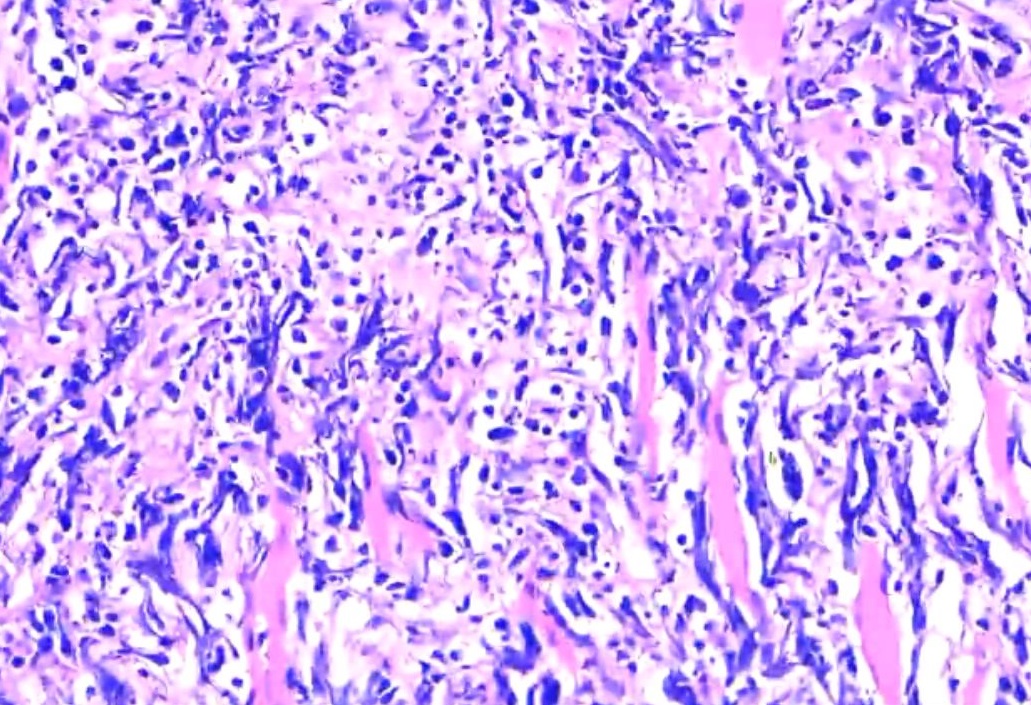

小土豆跟着农人老师学本领-膀胱电切手术 粘膜下印戒细胞散在分布 局部腺管样结构 低分化腺癌(印戒细胞癌)除外转移后考虑膀胱原发